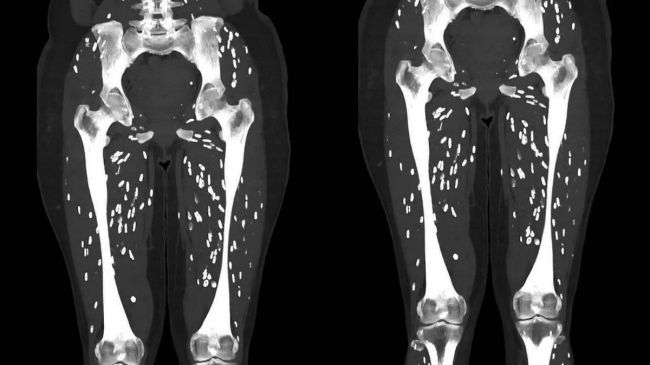

рдбреЙрдХреНрдЯрд░ рдиреЗ рд╕реЛрд╢рд▓ рдореАрдбрд┐рдпрд╛ рдкреНрд▓реЗрдЯрдлреЙрд░реНрдо X рдкрд░ рдорд░реАрдЬ рдХреЗ рд╕реАрдЯреА рд╕реНрдХреИрди рдХрд╛ рдлреЛрдЯреЛ рднреА рд╢реЗрдпрд░ рдХрд┐рдпрд╛ рд╣реИред рдлреЛрдЯреЛ рдореЗрдВ рджрд┐рдЦрд╛рдИ рджреЗ рд░рд╣рд╛ рд╣реИ рдХрд┐ рдорд░реАрдЬ рдХреЗ рдкреИрд░реЛрдВ рдореЗрдВ рд╕рдлреЗрдж рд░рдВрдЧ рдХреЗ рдХреБрдЫ рдХреАреЬреЗ рдЬреИрд╕реА рдЪреАрдЬ рджрд┐рдЦрд╛рдИ рджреЗ рд░рд╣реА рд╣реИред рдпрд╣реА рдХреАреЬреЗ рд╕рдмрдХреЛ рдкрд░реЗрд╢рд╛рди рдХрд░ рд░рд╣реЗ рд╣реИрдВред рджрд░рдЕрд╕рд▓ рдпреЗ рдкрд░рдЬреАрд╡реА рд╣реИрдВ, рдЬреЛ рдХрд┐рд╕реА рдЕрдиреНрдп рдЬреАрд╡рд┐рдд рдЪреАрдЬ рдкрд░ рд╣реА рдирд┐рд░реНрднрд░ рд░рд╣рддреЗ рд╣реИрдВред рд╣рд╛рд▓рд╛рдВрдХрд┐ рдорд░реАрдЬ рдХреЗ рдкреИрд░ рдХреЛ рджреЗрдЦрдХрд░ рдХрд┐рд╕реА рдХреЛ рд╕рдордЭ рд╣реА рдирд╣реАрдВ рдЖрдпрд╛ рдХрд┐ рдЖрдЦрд┐рд░ рдорд╛рдЬрд░рд╛ рдХреНрдпрд╛ рд╣реИред рдЗрд╕рдХреЗ рдмрд╛рдж рдбреЙрдХреНрдЯрд░ рдиреЗ рдЦреБрдж рд╣реА рдмрддрд╛рдпрд╛ рдХрд┐ рдЖрдЦрд┐рд░ рд╢рдЦреНрд╕ рдХреЗ рдкреИрд░реЛрдВ рдореЗрдВ рдХреНрдпрд╛ рд╣реИ!

рдбреЙрдХреНрдЯрд░ рдиреЗ рдХрд╣рд╛ рдХрд┐ рд░реЛрдЧреА рдХреЛ ‘рдЯреЗрдирд┐рдпрд╛ рд╕реЛрд▓рд┐рдпрдо’ рдпрд╛ рд╕рд┐рд╕реНрдЯреАрд╕рд░реНрдХреЛрд╕рд┐рд╕ рд╣реЛ рдЧрдпрд╛ред рдЕрдм рд╕рд╡рд╛рд▓ рдпреЗ рдЙрдарддрд╛ рд╣реИ рдХрд┐ рдЖрдЦрд┐рд░ рд╕рд┐рд╕реНрдЯреАрд╕рд░реНрдХреЛрд╕рд┐рд╕ рдХреНрдпрд╛ рд╣реИ? рдбреЙрдХреНрдЯрд░ рдХреЗ рдЕрдиреБрд╕рд╛рд░, рд╕рд┐рд╕реНрдЯреАрд╕рд░реНрдХреЛрд╕рд┐рд╕ рдкреЛрд░реНрдХ рдЯреЗрдкрд╡рд░реНрдо рдХреЗ рдХрд╛рд░рдг рд╣реЛрдиреЗ рд╡рд╛рд▓рд╛ рдПрдХ рдЧрдВрднреАрд░ рд╕рдВрдХреНрд░рдордг рд╣реИ, рдЬрд╣рд╛рдВ рдкреЛрд░реНрдХ рдЯреЗрдкрд╡рд░реНрдо рдХреЗ рд▓рд╛рд░реНрд╡рд╛ рдорд╕реНрддрд┐рд╖реНрдХ рдФрд░ рдорд╛рдВрд╕рдкреЗрд╢рд┐рдпреЛрдВ рд╕рд╣рд┐рдд рдХреЛрд╢рд┐рдХрд╛рдУрдВ рдХреЗ рд╕рдореВрд╣ рддрдХ рдкрд╣реБрдВрдЪ рдЬрд╛рддреЗ рд╣реИрдВ , рдЬрд┐рд╕рд╕реЗ рдЗрдВрд╕рд╛рди рдЧрдВрднреАрд░ рд░реВрдк рд╕реЗ рдмреАрдорд╛рд░ рд╣реЛ рд╕рдХрддрд╛ рд╣реИред

рдбреЙрдХреНрдЯрд░ рдХреЗ рдЕрдиреБрд╕рд╛рд░, рдЗрд╕рд╕реЗ рддреНрд╡рдЪрд╛ рдХреЗ рдиреАрдЪреЗ рдЧрд╛рдВрда, рд╕рд┐рд░рджрд░реНрдж рдФрд░ рджреМрд░реЗ рдкрд╛рд╕ рд╕рдХрддреЗ рд╣реИрдВред рдХрднреА рдХрднреА рдпрд╣ рд╕рдВрдХреНрд░рдордг рджрд┐рдорд╛рдЧ рдпрд╛ рд░реАрдврд╝ рдХреА рд╣рдбреНрдбреА рддрдХ рдкрд╣реБрдВрдЪ рдЬрд╛рддрд╛ рд╣реИред рдЕрдзрдкрдХреЗ рд╕реВрдЕрд░ рдХрд╛ рдорд╛рдВрд╕ рдЦрд╛рдиреЗ рд╕реЗ рдпреЗ рд╕рдВрдХреНрд░рдордг рдЬрд▓реНрджреА рдлреИрд▓рддрд╛ рд╣реИред рд╕реВрдЕрд░ рдХреЗ рдорд╛рдВрд╕ рдХреЛ рдЦрд╛рдиреЗ рд╕реЗ рдордиреБрд╖реНрдп ‘рдЯреА. рд╕реЛрд▓рд┐рдпрдо’ рд╕реЗ рд╕рдВрдХреНрд░рдорд┐рдд рд╣реЛ рдЬрд╛рддрд╛ рд╣реИред

рдбреЙрдХреНрдЯрд░ рд╕реИрдо рдЧрд╛рд▓реА рдиреЗ рдмрддрд╛рдпрд╛ рдХрд┐ рдЕрдиреБрдорд╛рди рд╣реИ рдХрд┐ рджреБрдирд┐рдпрд╛ рднрд░ рдореЗрдВ рд╣рд░ рд╕рд╛рд▓ рд▓рдЧрднрдЧ 50 рдорд┐рд▓рд┐рдпрди рд▓реЛрдЧ рд╕рд┐рд╕реНрдЯреАрд╕рд░реНрдХреЛрд╕рд┐рд╕ рд╕реЗ рд╕рдВрдХреНрд░рдорд┐рдд рд╣реЛрддреЗ рд╣реИрдВ рдФрд░ рд▓рдЧрднрдЧ 50,000 рдореМрддреЗрдВ рд╣реЛрддреА рд╣реИрдВред рдЗрд╕ рддрд░рд╣ рдХреЗ рд╕рдВрдХреНрд░рдордг рдЖрдорддреМрд░ рдкрд░ рд╕реАрдЯреА рд╕реНрдХреИрди рдкрд░ рд╕рдлреЗрдж рдзрдмреНрдмреЛрдВ рдХреЗ рд░реВрдк рдореЗрдВ рджрд┐рдЦрд╛рдИ рджреЗрддрд╛ рд╣реИред рдЙрдиреНрд╣реЛрдВрдиреЗ рдпрд╣ рднреА рдХрд╣рд╛ рдХрд┐ рдЗрд╕ рдХрд╣рд╛рдиреА рд╕реЗ рдпрд╣ рд╕рдмрдХ рдорд┐рд▓рддрд╛ рд╣реИ рдХрд┐ рд╕рд╛рдл-рд╕рдлрд╛рдИ рд░рдЦрдиреЗ рдХреА рдкреВрд░реА рдХреЛрд╢рд┐рд╢ рдХрд░реЗрдВ, рд╣рдореЗрд╢рд╛ рдЕрдкрдиреЗ рд╣рд╛рде рдзреЛрдПрдВ рдФрд░ рдХрднреА рднреА рдХрдЪреНрдЪрд╛ рдпрд╛ рдЕрдзрдкрдХрд╛ рд╕реВрдЕрд░ рдХрд╛ рдорд╛рдВрд╕ рди рдЦрд╛рдПрдВред